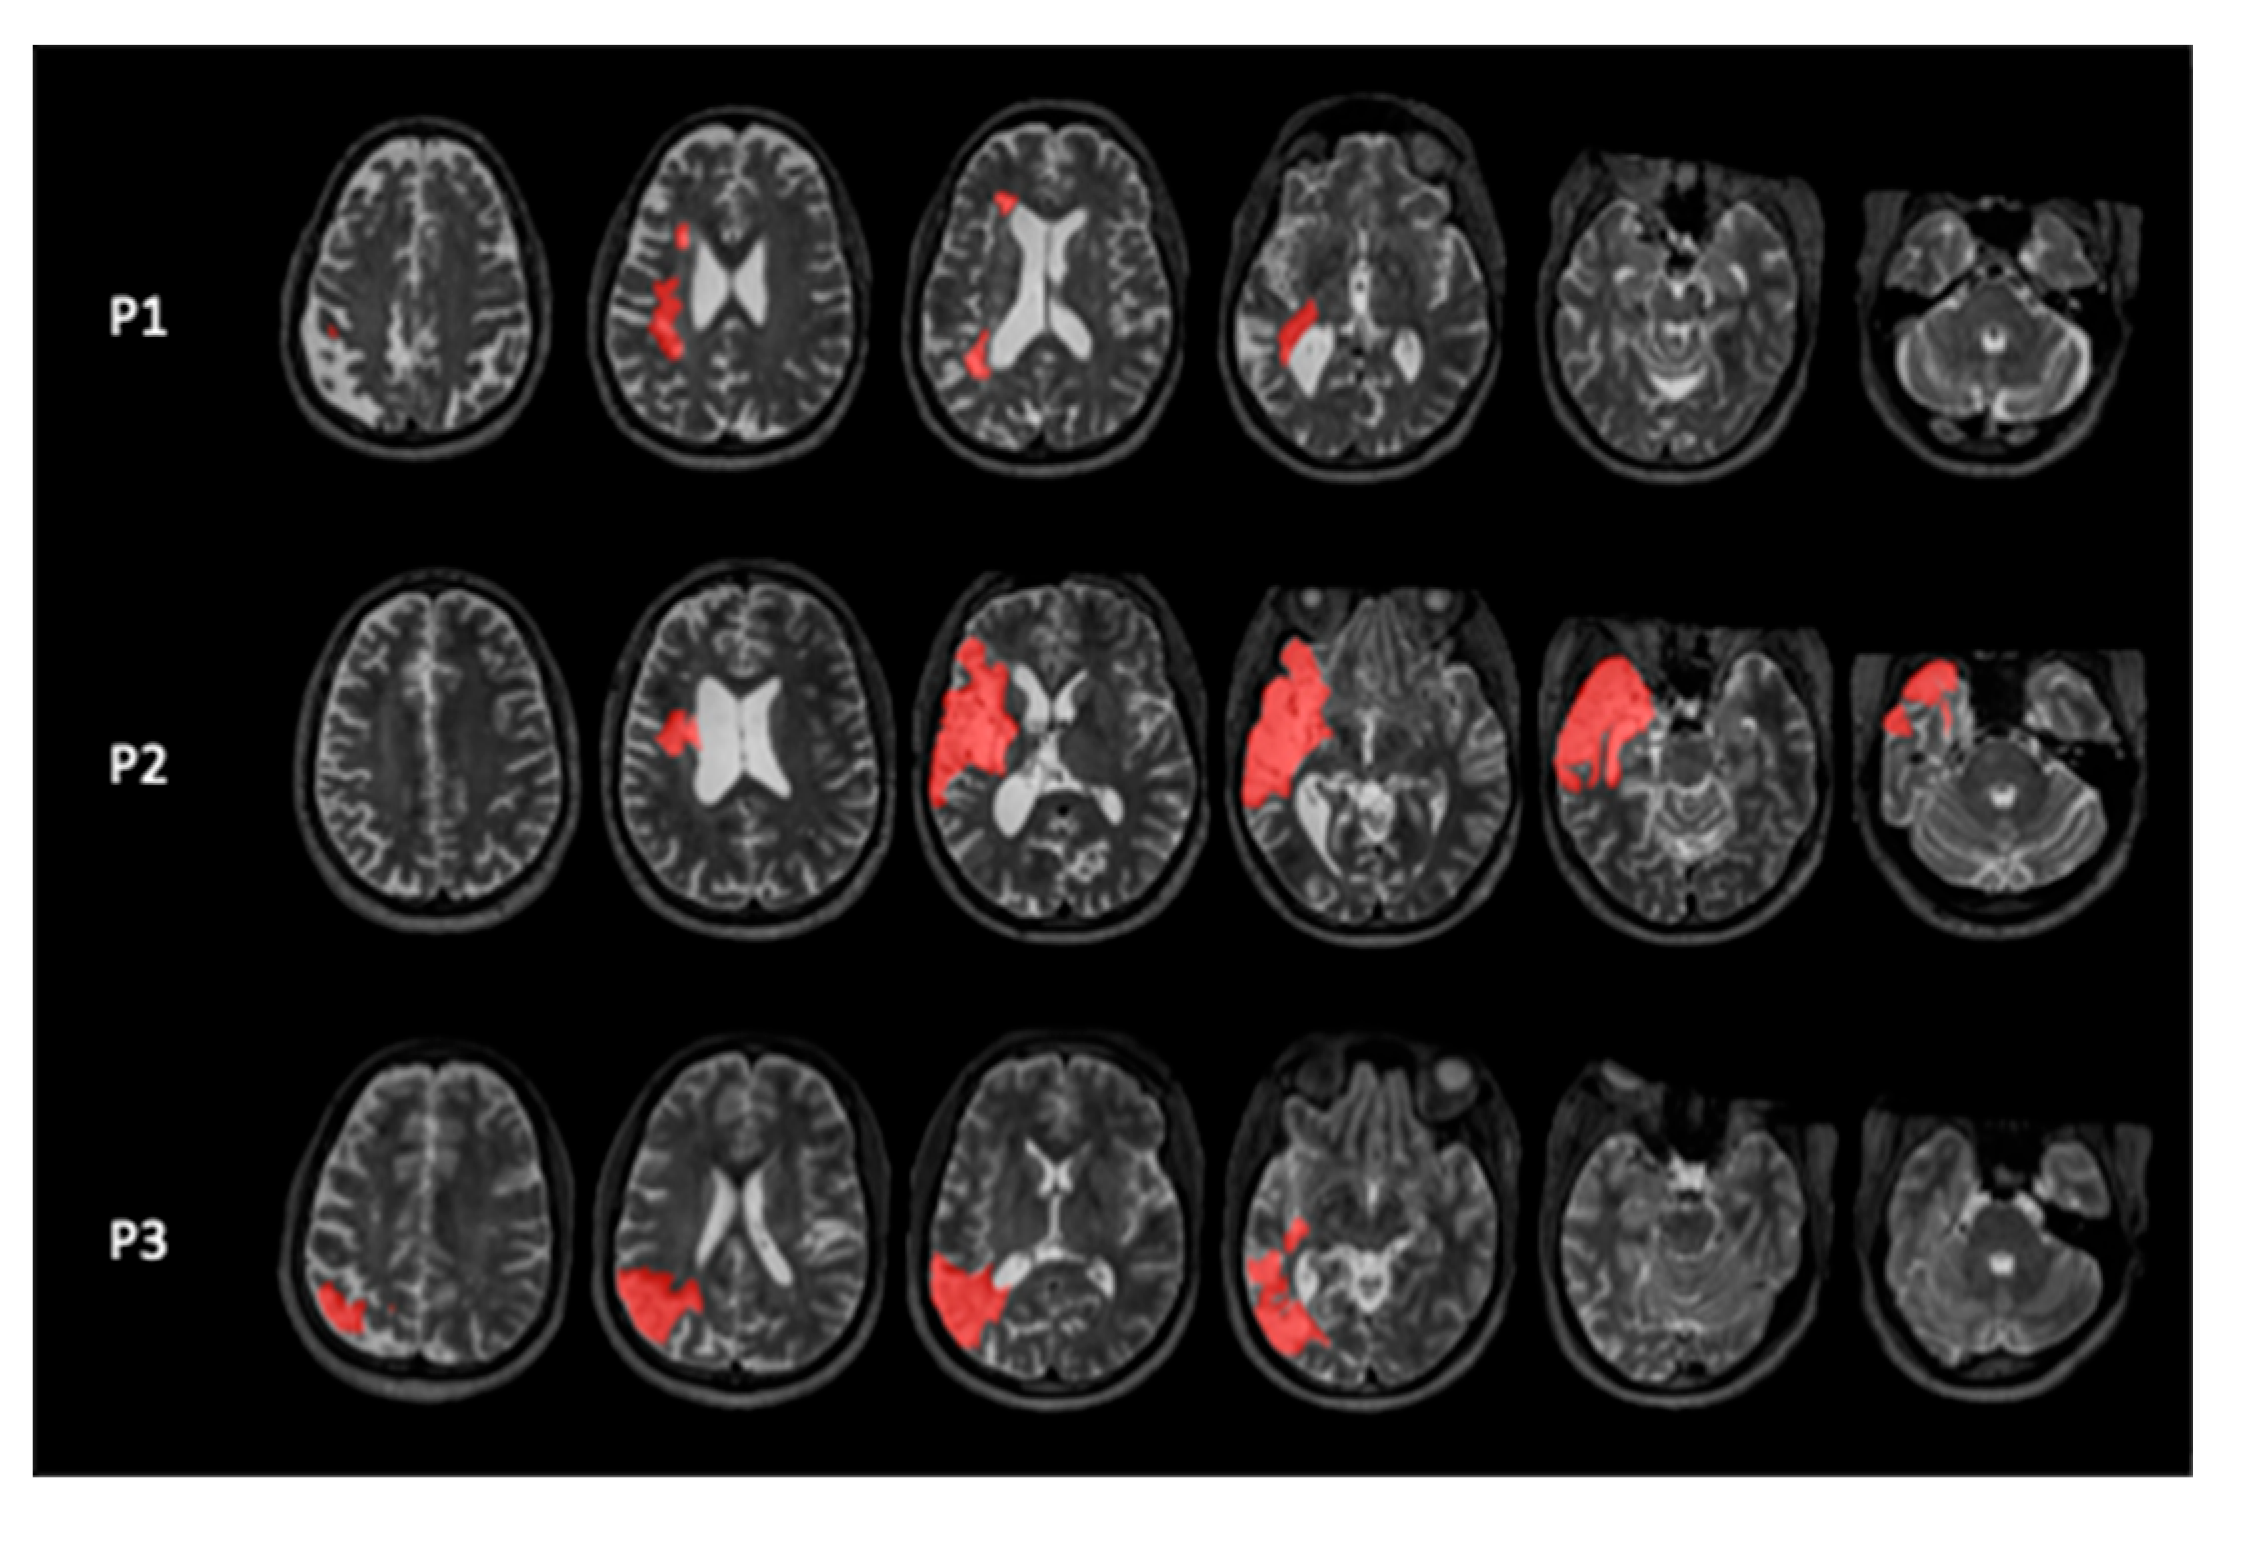

We included three participants with chronic mild to moderate chronic aphasia following a left hemispheric stroke (Figure 1) at the University of South Carolina. The study was approved by the IRB of the University of South Carolina, and all participants signed an Informed Consent form. They received monetary compensation for their effort.

Figure 1. T2-weighted MRI scans showing the location of left hemispheric lesions in red.